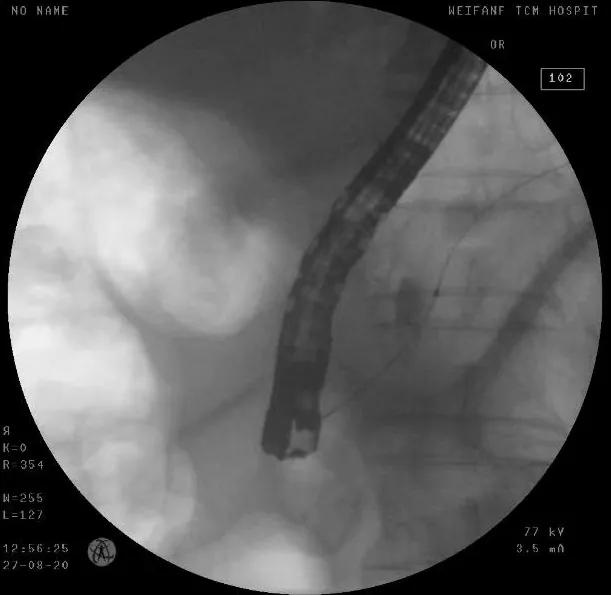

8月28日,在麻醉科等科室的全力配合下,普外科付云强为主任为患者实施手术,术中付云强主任将十二指肠镜经口腔进入十二指肠,在十二指肠主乳头的方寸之间,细心的寻找胰管开口,功夫不负有心人,在其精湛的技术下,顺利的找到并放置了胰管支架,再经十二指肠乳头开口处注入造影剂行胆管造影,造影显示胆总管全程有充盈缺损,考虑肿瘤胆道系统广泛转移,术中诊断为壶腹部癌ERCP术后,胆总管及肝内转移。根据治疗计划行十二指肠逆行胰胆管造影术+原胆道支架拔除+胆道清理+胆道支架内引流术。手术顺利,术后患者安返病房。